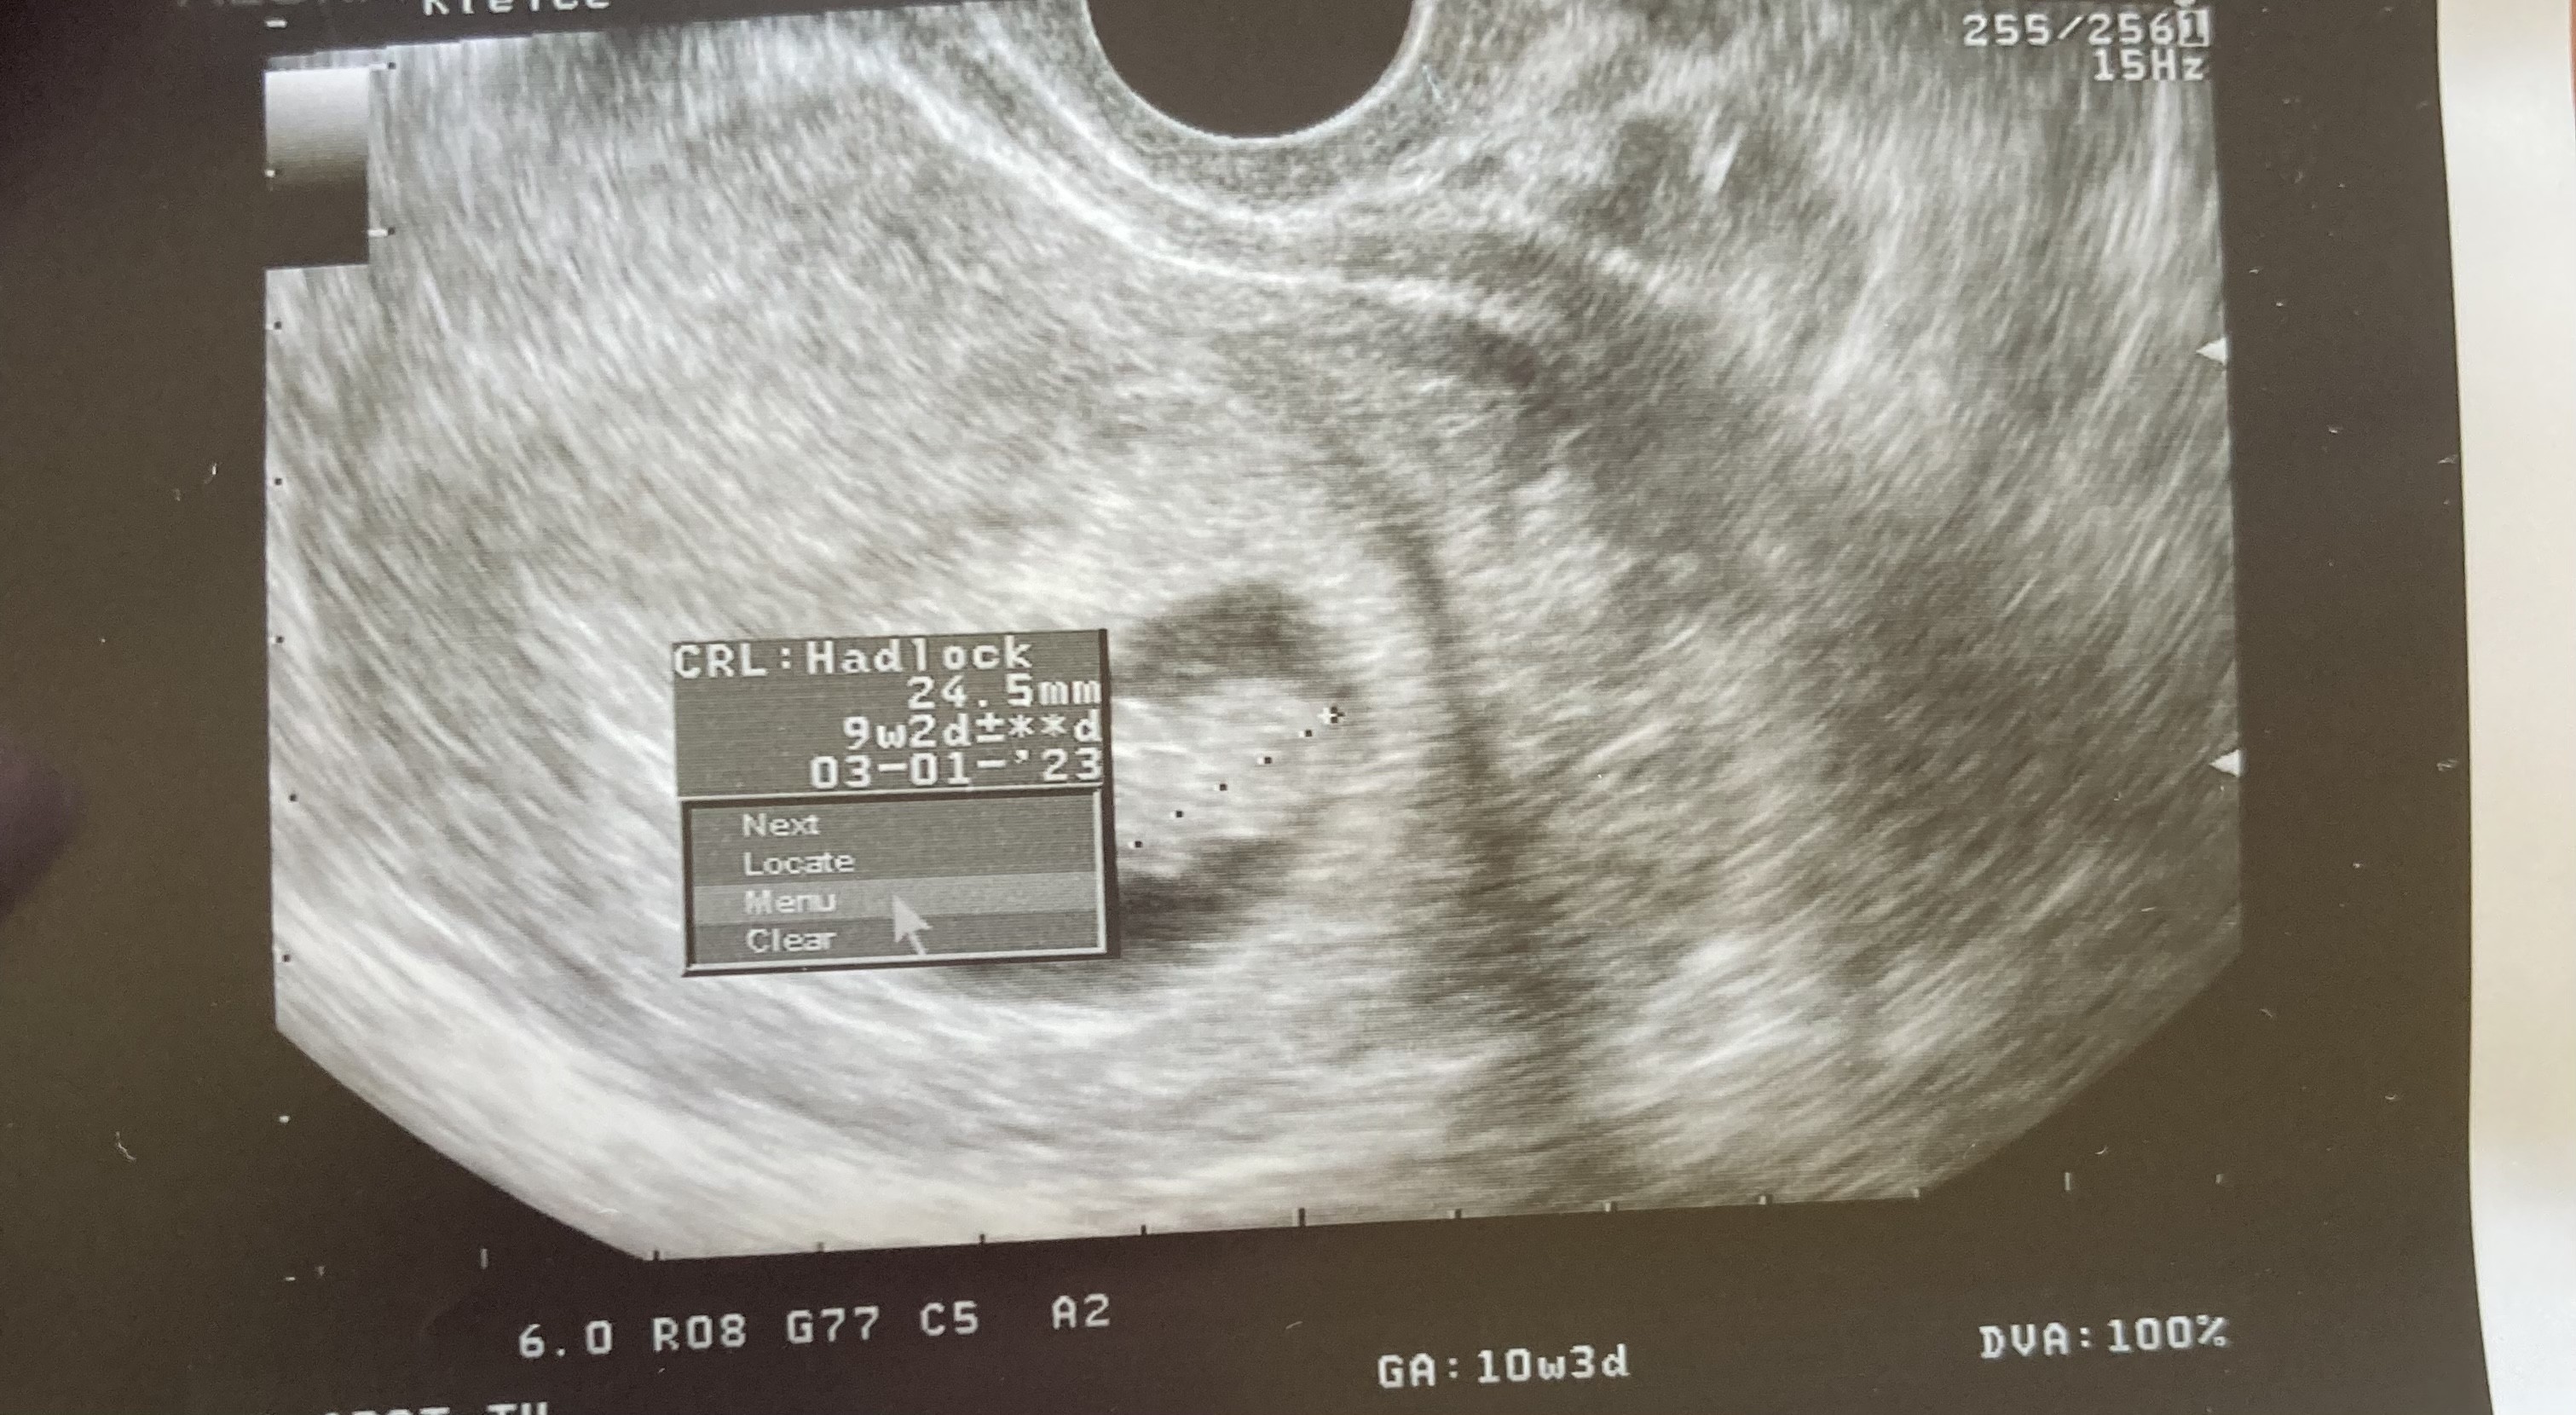

Ja już po wizycie. Termin teraz wychodzi na 03.01.2023, maluszek ma 24,5 mm. Wszystkie badania wyszły supcio, TSH mam najniższe odkąd żyje 😂 nie dostałam niestety skierowania na prenatalne, bo nie miał „uzasadnienia”, zeby mi dac :/ no nic trudno. Generalnie wszystko oki i mam zgodę już na basen 👍wstawiam fotkę 😄

Załączniki

• 1EC8B06C-CABD-4AB9-969D-5B9863D5003E.jpeg

1EC8B06C-CABD-4AB9-969D-5B9863D5003E.jpeg

919,4 KB · Wyświetleń: 131